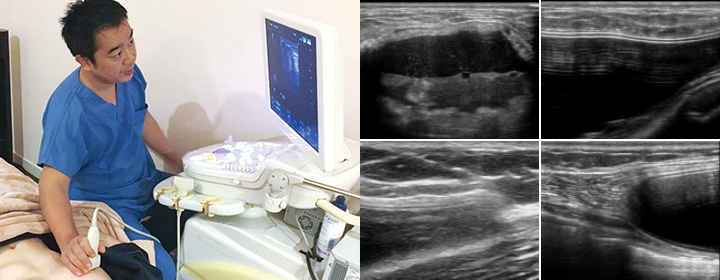

豊胸シリコンの挿入後は、定期検診が非常に重要です。定期検診を受けることで、無症状ながら実は問題が発生している場合でも早期発見でき、炎症や痛みが生じる前に対処るうことが可能です。触診だけでなく画像検査することが重要で、日本乳房オンコプラスティックサージャリー学会では豊胸シリコンの破損や変形がないか調べるため、2年に1回のMRIやエコーを使用した検査を推奨しています[4]。

当院の検診ではエコー検査を必ず行い、シリコンバッグの破損や漏れ、カプセル拘縮の有無などをしっかり確認します。お気軽にご相談ください。